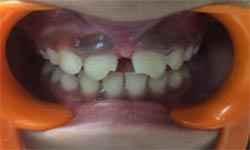

Before Treatment

After Treatment

Patient with a complaint of a gap in between upper central incisors. Dental Veneers done to close the gap between the central incisors